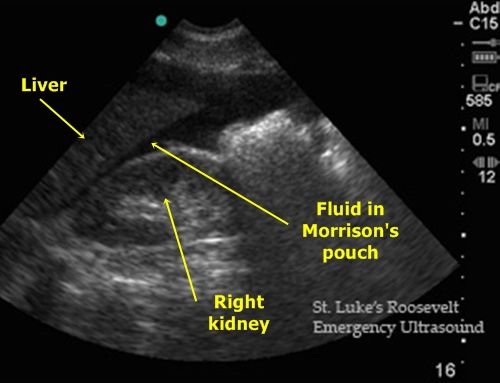

Morison’s Pouch

Other known aliases – hepatorenal recess/fossa, right posterior subhepatic space

Definition – a potential space between the liver and the right kidney

Clinical Significance – This a space where fluid can accumulate in the setting of ascites or abdominal trauma and be seen on CT or ultrasound. It is one of the view of a Focused Assessment of Sonography in Trauma (FAST) exam. Typically, 30-40mL of fluid needs to be present to be visualized.